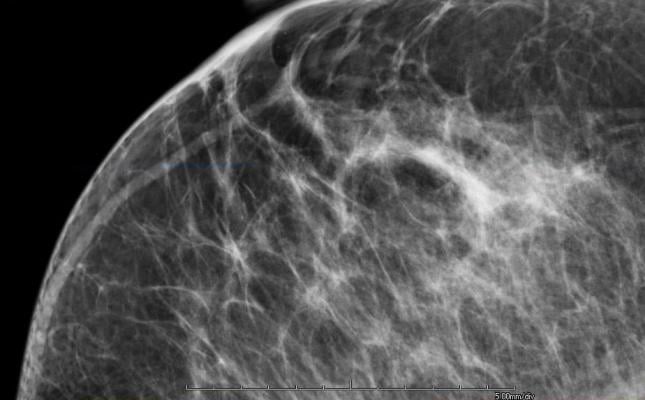

M-Vu Breast Density automatically and rapidly assesses breast density and provides consistent and accurate measurements. The tool evaluates mammograms by analyzing the structure, texture and dispersion of the tissue, rather than simply estimating total fibroglandular volume. To ensure product effectiveness, the findings of a panel of 13 expert radiologists were used to calibrate the VuComp density categories to the American College of Radiology’s (ACR) Breast Imaging Reporting and Data System (BI-RADS) standard. The M-Vu algorithms quantify areas with a dense appearance that could hide cancer, and convert them to categories corresponding to the recently updated standard. This exclusive approach using appearance-based texture and dispersion analysis provides useful adjunctive information. M-Vu Breast Density is the only commercially available, U.S. Food and Drug Administration (FDA) -cleared system that employs this scientific methodology.

Clinical studies have shown that dense breasts can hide a cancerous lesion by reducing the ability to visualize fine structures and details that could indicate a malignant abnormality, making breast cancer detection in a mammogram more difficult. Patients with dense breast tissue may be recommended for additional screening exams. Legislation has passed in 16 states requiring physicians to notify patients if their breast density is in one of the two higher categories.